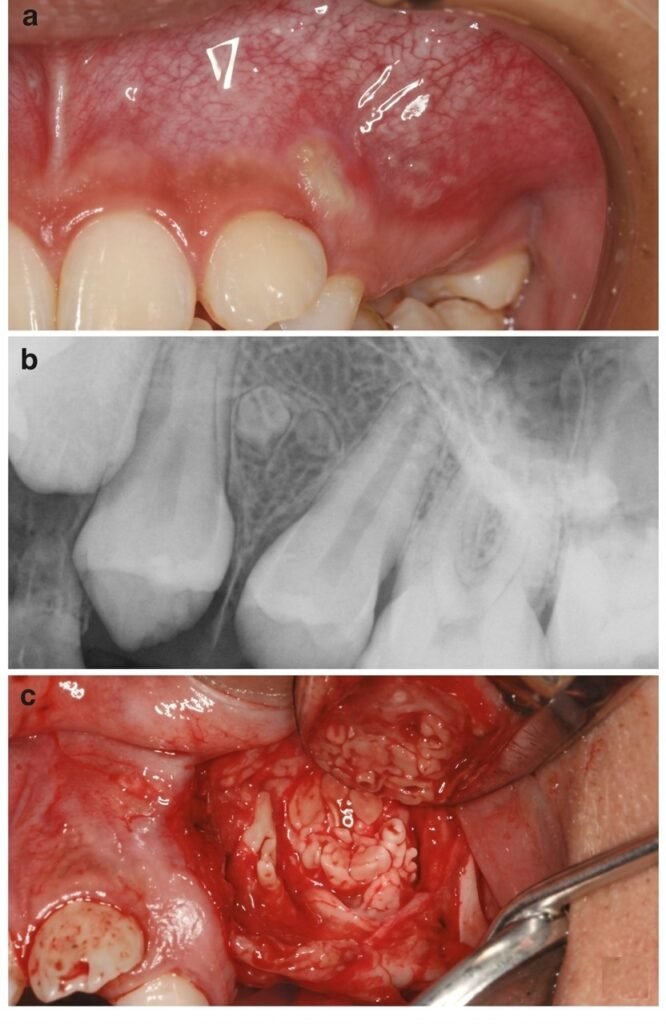

Traitement chirurgical (traitement de recours)

Indications :

- Échec du traitement conventionnel

- Impossibilité d’éliminer le processus pathologique par voie coronaire (canaux inaccessibles, calcifications, ancrage radiculaire, instrument fracturé, résorption externe)

Contre-indications :

- Résultat équivalent possible par traitement conventionnel

- État général contre-indiquant la chirurgie

- Implications anatomiques défavorables

- Incompétence technique du praticien

Technique opératoire : Asepsie → Anesthésie → Incision → Décollement → Localisation de l’apex → Trépanation → Exérèse de la masse granulomateuse → Curetage apical → Résection apicale → Obturation à rétro → Nettoyage de la cavité chirurgicale → Suture

3.4 Thérapeutique du Kyste Radiculo-dentaire

Kyste vrai

- Cavité totalement bordée d’épithélium, sans relation avec le canal radiculaire

- Moins apte à guérir par traitement endodontique seul, surtout si volumineux

- Traitement chirurgical : énucléation ou kystectomie, avec examen histopathologique de la pièce